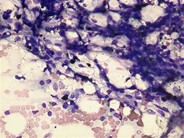

A 4-year-old girl with a known history of methylmalonic acidemia (MMA) complicated by acquired hypothyroidism, failure to thrive, and developmental delay developed pancytopenia during an admission for emesis and metabolic acidosis. She had no symptoms of a viral infection, and her cytopenias worsened over 3 weeks despite resolution of her acidosis. Her complete blood count showed a total white blood cell count of 3.1 × 10 9/L with an absolute neutrophil count of 510 /μL, hemoglobin of 6.8 g/dL, and platelets of 24 × 10 9/L. Given the long duration and unusual severity of the cytopenias, evolving aplastic anemia was considered, and a bone marrow aspirate and biopsy were performed. These showed trilineage hypoplasia and prominent dysplasia (see inset panel, arrows), including multiple vacuolated myeloid precursors (see large panel, arrows). Testing for underlying viral causes by serology and polymerase chain reaction was negative, as was testing for inherited bone marrow failure syndromes and myelodysplastic syndrome/leukemia. Her peripheral counts recovered spontaneously and fully over the ensuing 4 weeks. Interestingly, she was found to have recurrence of cytopenias on subsequent admissions for MMA-associated metabolic crises, correlating with the level of acidosis.Patients with MMA and other organic acidemias can develop bone marrow hypoplasia and trilineage dysplasia during metabolic crises, a phenomenon that has been described in a few case reports in the older literature. Cytopenias tend to correlate with organic acid levels in the blood, and count recovery typically occurs within 2 weeks, after normalization of the metabolic state. No specific treatment is needed outside of supportive care.